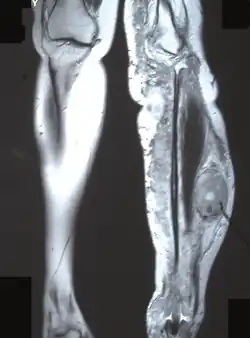

- Unilateral overgrowth of a limb. When a plexiform neurofibroma manifests on a leg or arm, it will cause extra blood circulation, and may thus accelerate the growth of the limb. This may cause considerable difference in length between left and right limbs. To equalize the difference during childhood, there is an orthopedic surgery called epiphysiodesis, where growth at the epiphyseal (growth) plate is halted. It can be performed on one side of the bone to help correct an angular deformity, or on both sides to stop growth of that bone completely. The surgery must also be carefully planned with regard to timing, as it is non-reversible. The goal is that the limbs are at near-equal length at end of growth.